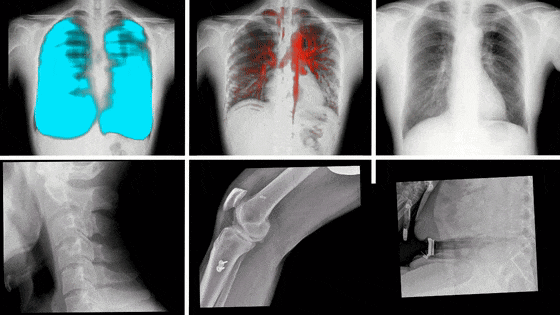

動態(tài)DR影像

PLX8100動態(tài)DR